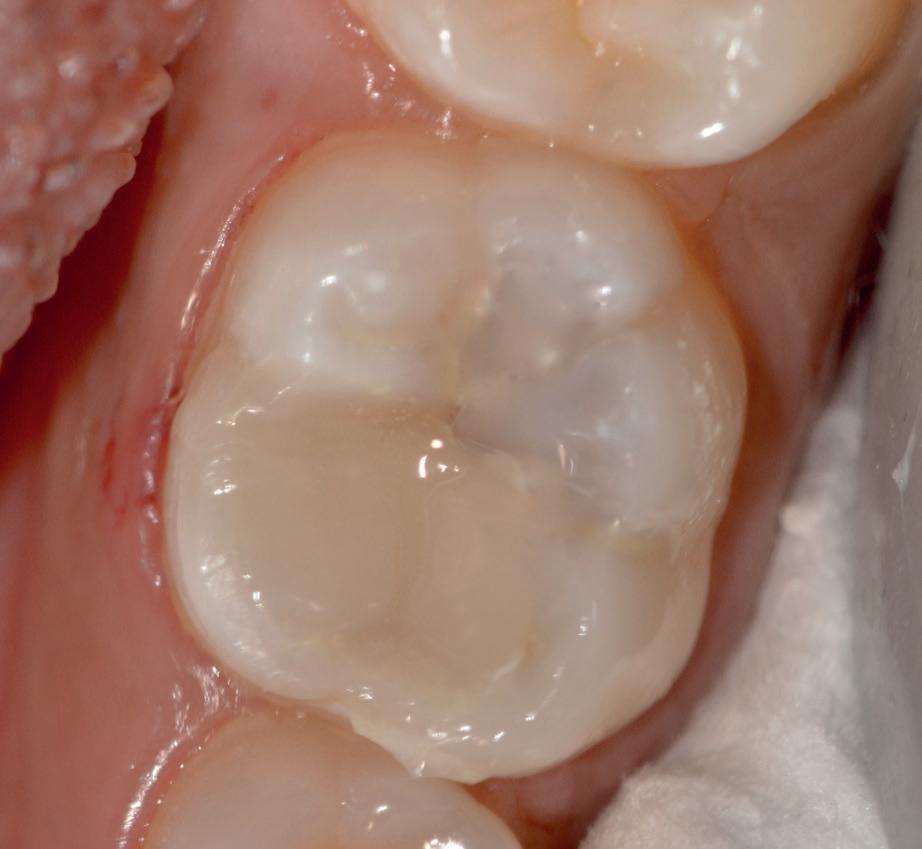

Predictable management of a deep carious lesion, page 27